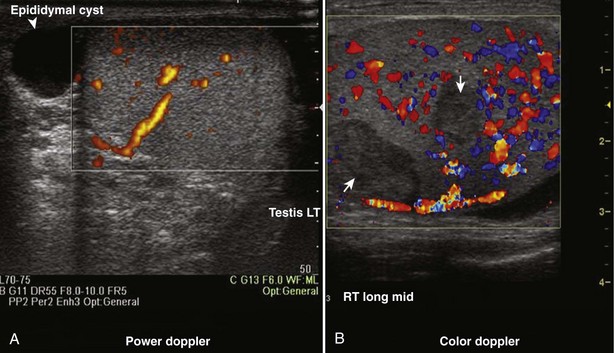

Color Doppler ultrasonography allows for evaluation of the velocity and direction of motion. A color map may be applied to direction with the most common assignation of the color blue to motion away from the transducer and red for motion toward the transducer. The velocity of motion is designated by the intensity of the color; thus the brighter the color is, the more rapid the motion. Color Doppler may be used to evaluate the presence of absence of blood flow in the kidney, testes, penis, and prostate. It also may be useful in the detection of ureteral “jets” of urine emerging from the ureteral orifices.

Power Doppler ultrasonography is a mode that assigns the amplitude of frequency change to a color map. This does not permit evaluation of velocity or direction of flow but is less affected by back-scattered waves and therefore a more sensitive mode for detecting blood flow. Power Doppler is less angle dependent than color Doppler and is three to five times as sensitive as color Doppler ultrasound for detecting flow.